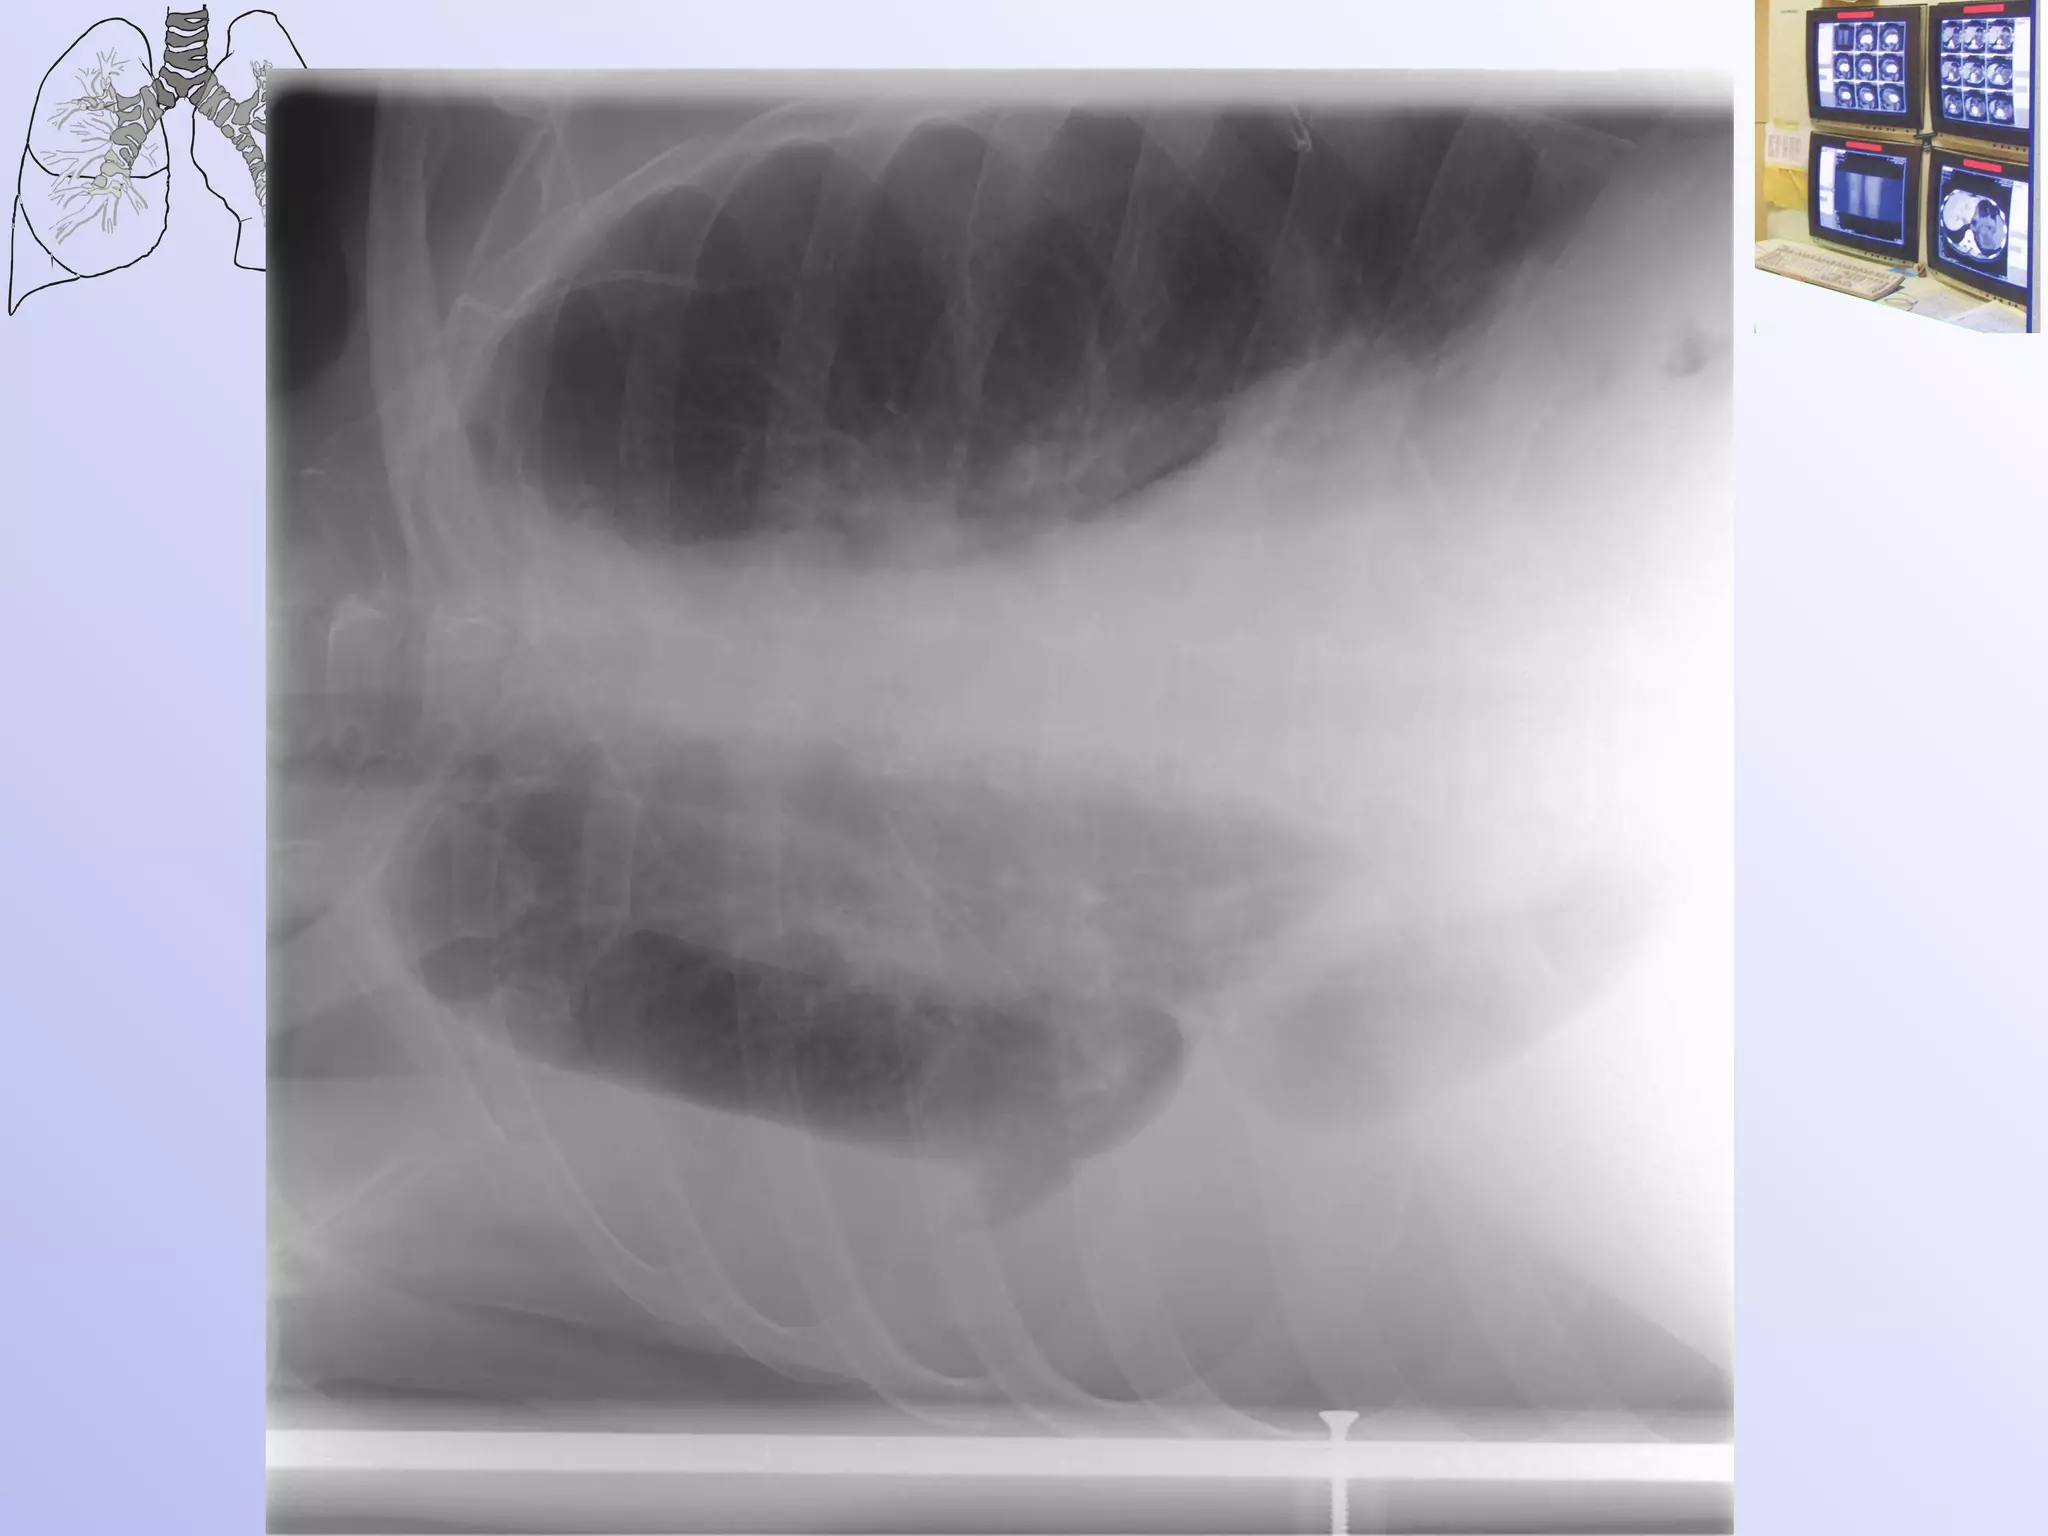

2 степень бронхостеноза Клапанная закупорка бронха - на вдохе воздух проникает через стенозированный участок, а на выдохе полностью не выходит. В рентгеновском изображении: сегмент, доля или легкое увеличены в объеме, прозрачность их повышена, органы средостения оттеснены в здоровую сторону, диафрагма на стороне поражения опущена.